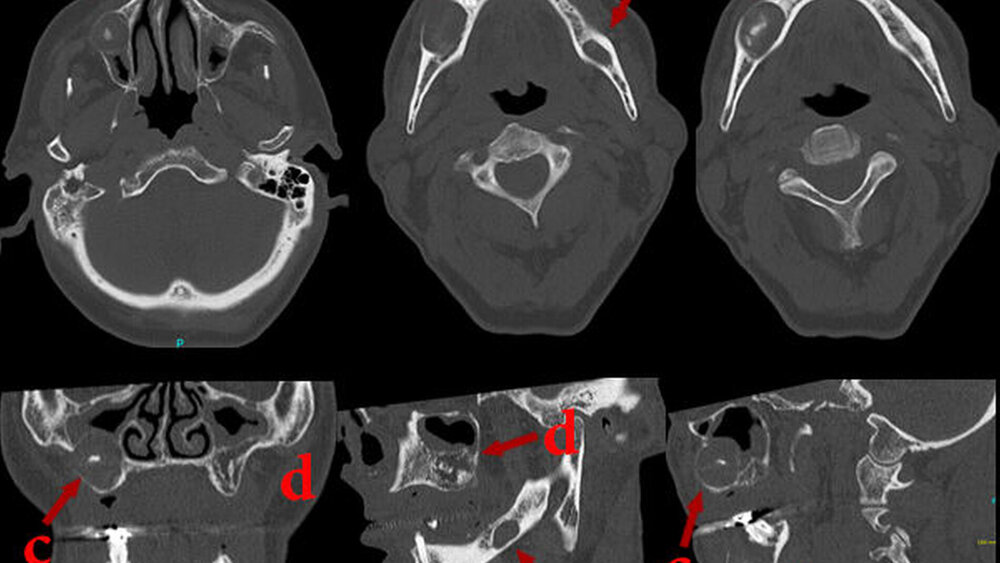

Vom benignen Knochentumor zur odontogenen Zyste